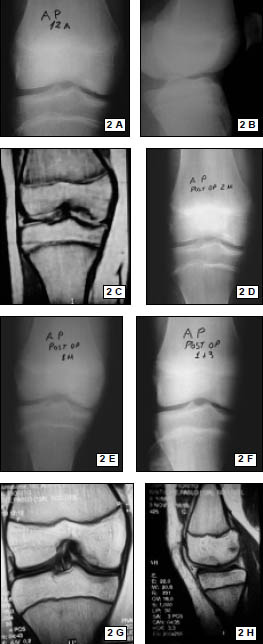

Resonancia Magnética Nuclear. Se utilizo un resonador General Electric 1.5 Tesla. (Fig. 2)

Figura 2: RMN. Desinserción del tendón rotuliano en polo inferior patelar, encondroma fémur distal.

Se realizaron radiografías de control en el postoperatorio inmediato. (Figs. 6, 7)

Se realizó el diagnóstico clínico de la lesión (impotencia funcional, dolor y brecha infrapatelar) y luego los métodos de imágenes complementarios confirmaron las lesiones. Mediante RNM se pudo esta- blecer el nivel de la lesión, con 9 desinserciones a nivel del polo distal de la rótula y 1 rotura mediotendinosa en el tendón patelar.